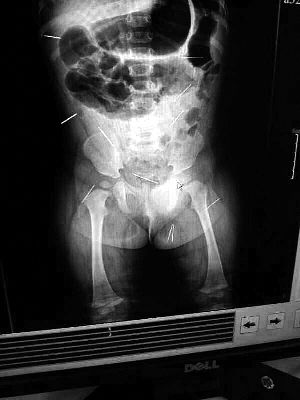

山東聊城11個月女嬰萱萱(化名)疑似被人以12根鋼針插滿臀部、腹腔等部位,昨天在兒童醫(yī)院會診后,醫(yī)生稱3根針靠近胸腔最危險,首批先行取出,預計將在下周二手術。孩子父母稱孩子一直由家人照顧,自家與他人并無冤怨。山東警方表示正在偵破中,不便透露案情。

“要不是當初那幾個紅點,可能到現(xiàn)在我們還不知道孩子身體里有鋼針!”昨天,在兒童醫(yī)院住院處,萱萱爸爸范先生稱,日前原本很愛笑的萱萱突然變得有些焦躁,一抱起來就哭,孩子母親偶然間在萱萱屁股上發(fā)現(xiàn)了幾個小紅點兒,原以為是蚊蟲叮咬,就醫(yī)結果卻讓人不寒而栗?!搬t(yī)院拍出的片子上,萱萱的體內(nèi)有12根鋼針,插滿臀部、腹腔、骨盆等各個部位?!狈断壬榻B,因為鋼針已深入體內(nèi),要是孩子不哭鬧,他們很難發(fā)現(xiàn)。

北京晨報記者了解到,目前體內(nèi)的12根鋼針多分布在孩子的臀部,一根在腹部,其余3根在胸腔附近,其中一根很接近心臟?!耙驗楹⒆犹?,醫(yī)生們害怕取針的時候對她造成傷害,在胸腔附近的3針可能會威脅她的生命”。